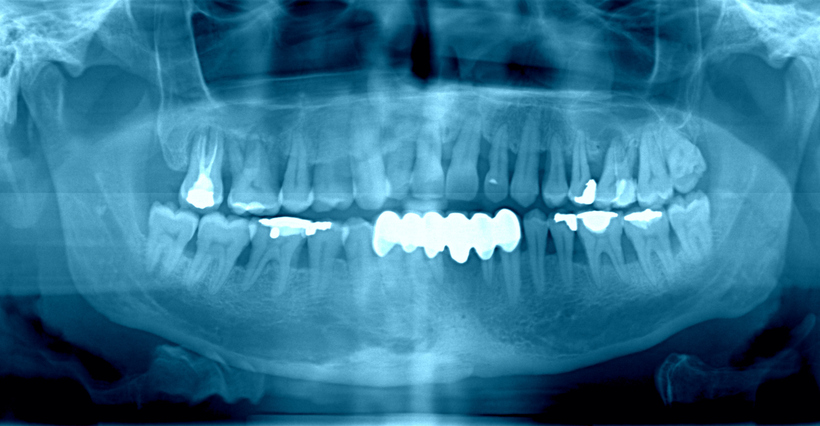

1. 파노라마 엑스레이

①한눈에 전체 확인: 위아래 모든 치아, 턱뼈, 부비동(코 옆 공간) 등을 넓게 촬영

②용도

●사랑니 위치 확인

●턱뼈 이상

●큰 충치나 낭종(물혹)

●전체 치아 상태 확인